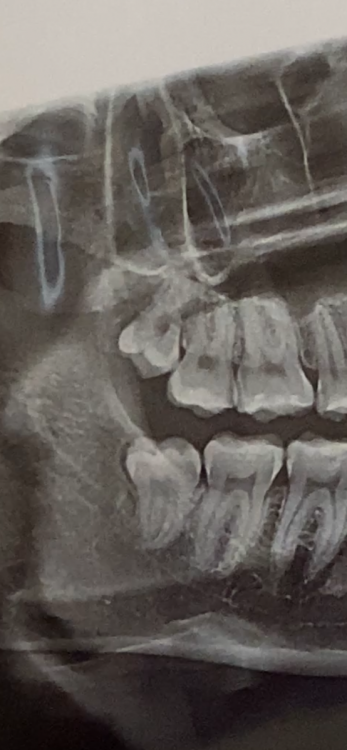

Karina21 Опубликовано 30 июля, 2021 Поделиться Опубликовано 30 июля, 2021 (изменено) Здравствуйте, обращаюсь к вам по поводу удаления зубов мудрости. В прошлую пятницу я удалила два зуба мудрости с правой стороны, отека не было, удалил врач быстро(я искала опытного хирурга по отзывам), наложили швы так как зубы были ретушированными, назначили пить дважды в день нимесил и ванночки из хлоргексидина. В понедельник(через два дня) я почувствовала сильную боль снизу рано утром и в тот де день поехала к врачу на осмотр, он сказал, что попала слюна и из-за этого воспаление(снял один шов, промыл, наложил какой-то лекарство с запахом аптеки) и сказал приехать на следующий день(во вторник снова промыл, положил альвожил и сказал не вынимать тампон минут 20) и вот сейчас уже пятница, восьмой день, а у меня все еще сильно болит(если не принимать обезбол, то боль отдает на 5 и 6 зуб и пульсирует в ухо) десна не красная, строгать ее не больно(максимум немного неприятно)иногда кровит Ем я исключительно пюре и йогурты, вообще не жевала неделю, спортом не занималась и придерживалась всех рекомендаций. Присутствует запах изо рта, но первые пару дней я считала, что это из-за отсутствия чистки зубов, а только ванночки, но сейчас то я чищу вот я не знаю что делать, записалась на еще один прием к врачу, но боюсь, что снова промоет, а мне не поможет, а без нимесила жить не могу на фото видно, что десна опухла, но такое я ощущаю и сверху(чувствую щекой, когда улыбаюсь) На снимке это до операции Изменено 30 июля, 2021 пользователем Karina21 Не дописала Ссылка на комментарий